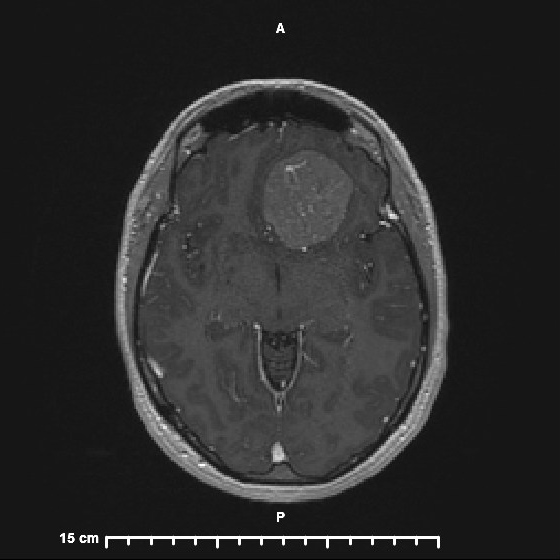

My journey from diagnosis to surgery to recovery to a “new normal” and everything in between.

Dive into my personal journey as I share what Christopher Walken has to do with my brain tumor! Uncover the ups, downs, and incredible moments that shaped my experience.